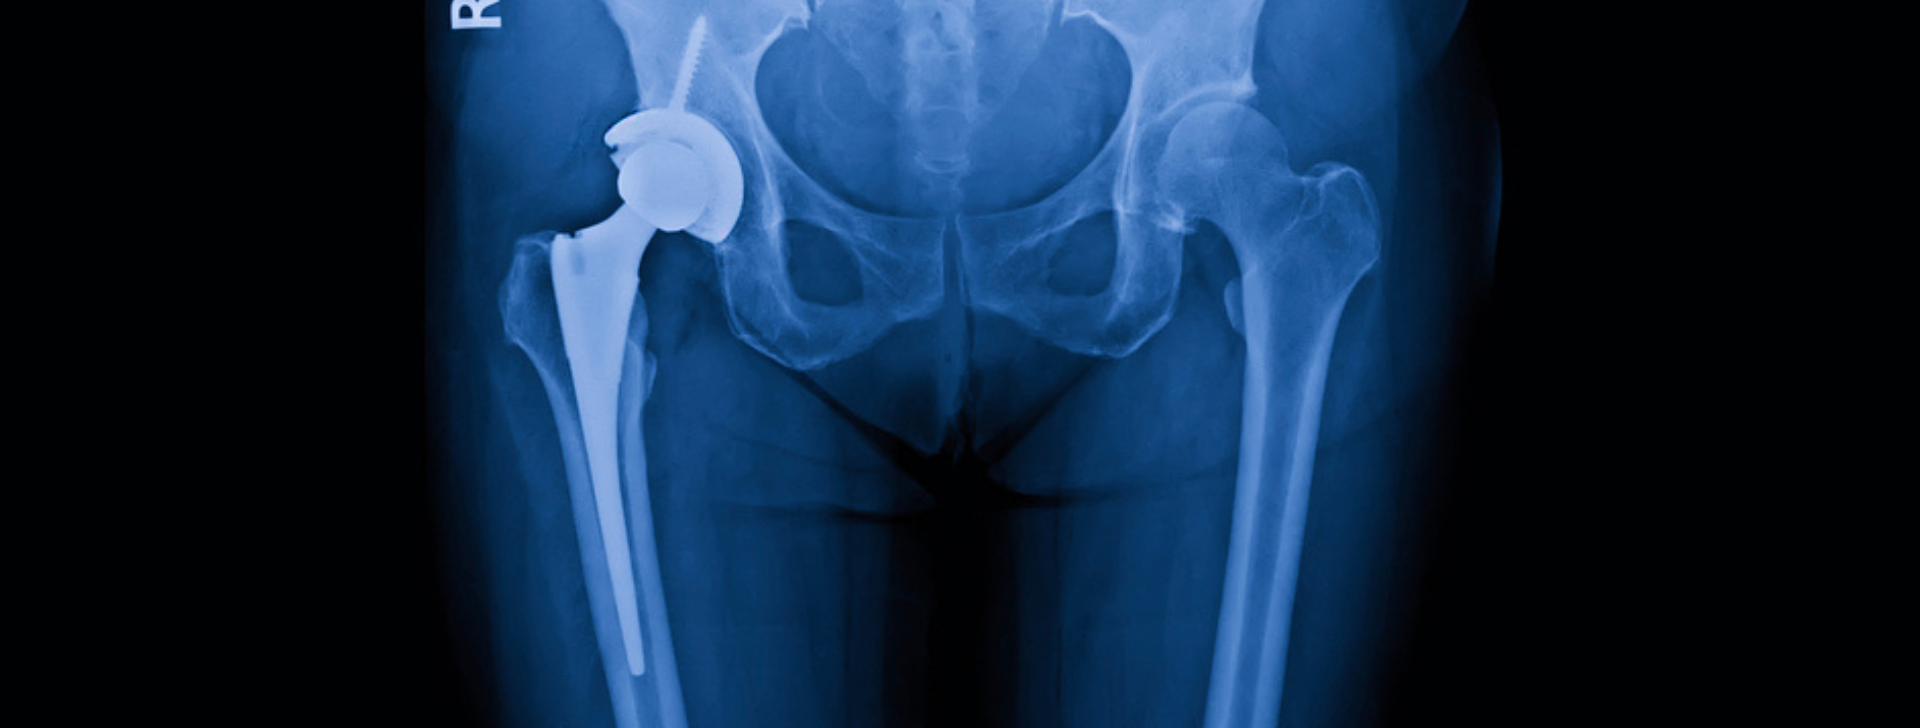

Πόνος στο ισχίο

Ο πόνος στο ισχίο είναι ένα σύμπτωμα που μπορεί να οφείλεται σε πληθώρα διαφορετικών παθολογικών καταστάσεων. Αποτελεί έναν από τους συχνότερους λόγους επίσκεψης στον ορθοπαιδικό, ιδιαίτερα σε άτομα μέσης και μεγαλύτερης ηλικίας. Η εντόπισή του δεν περιορίζεται απαραίτητα στην ίδια την άρθρωση, η οποία βρίσκεται …